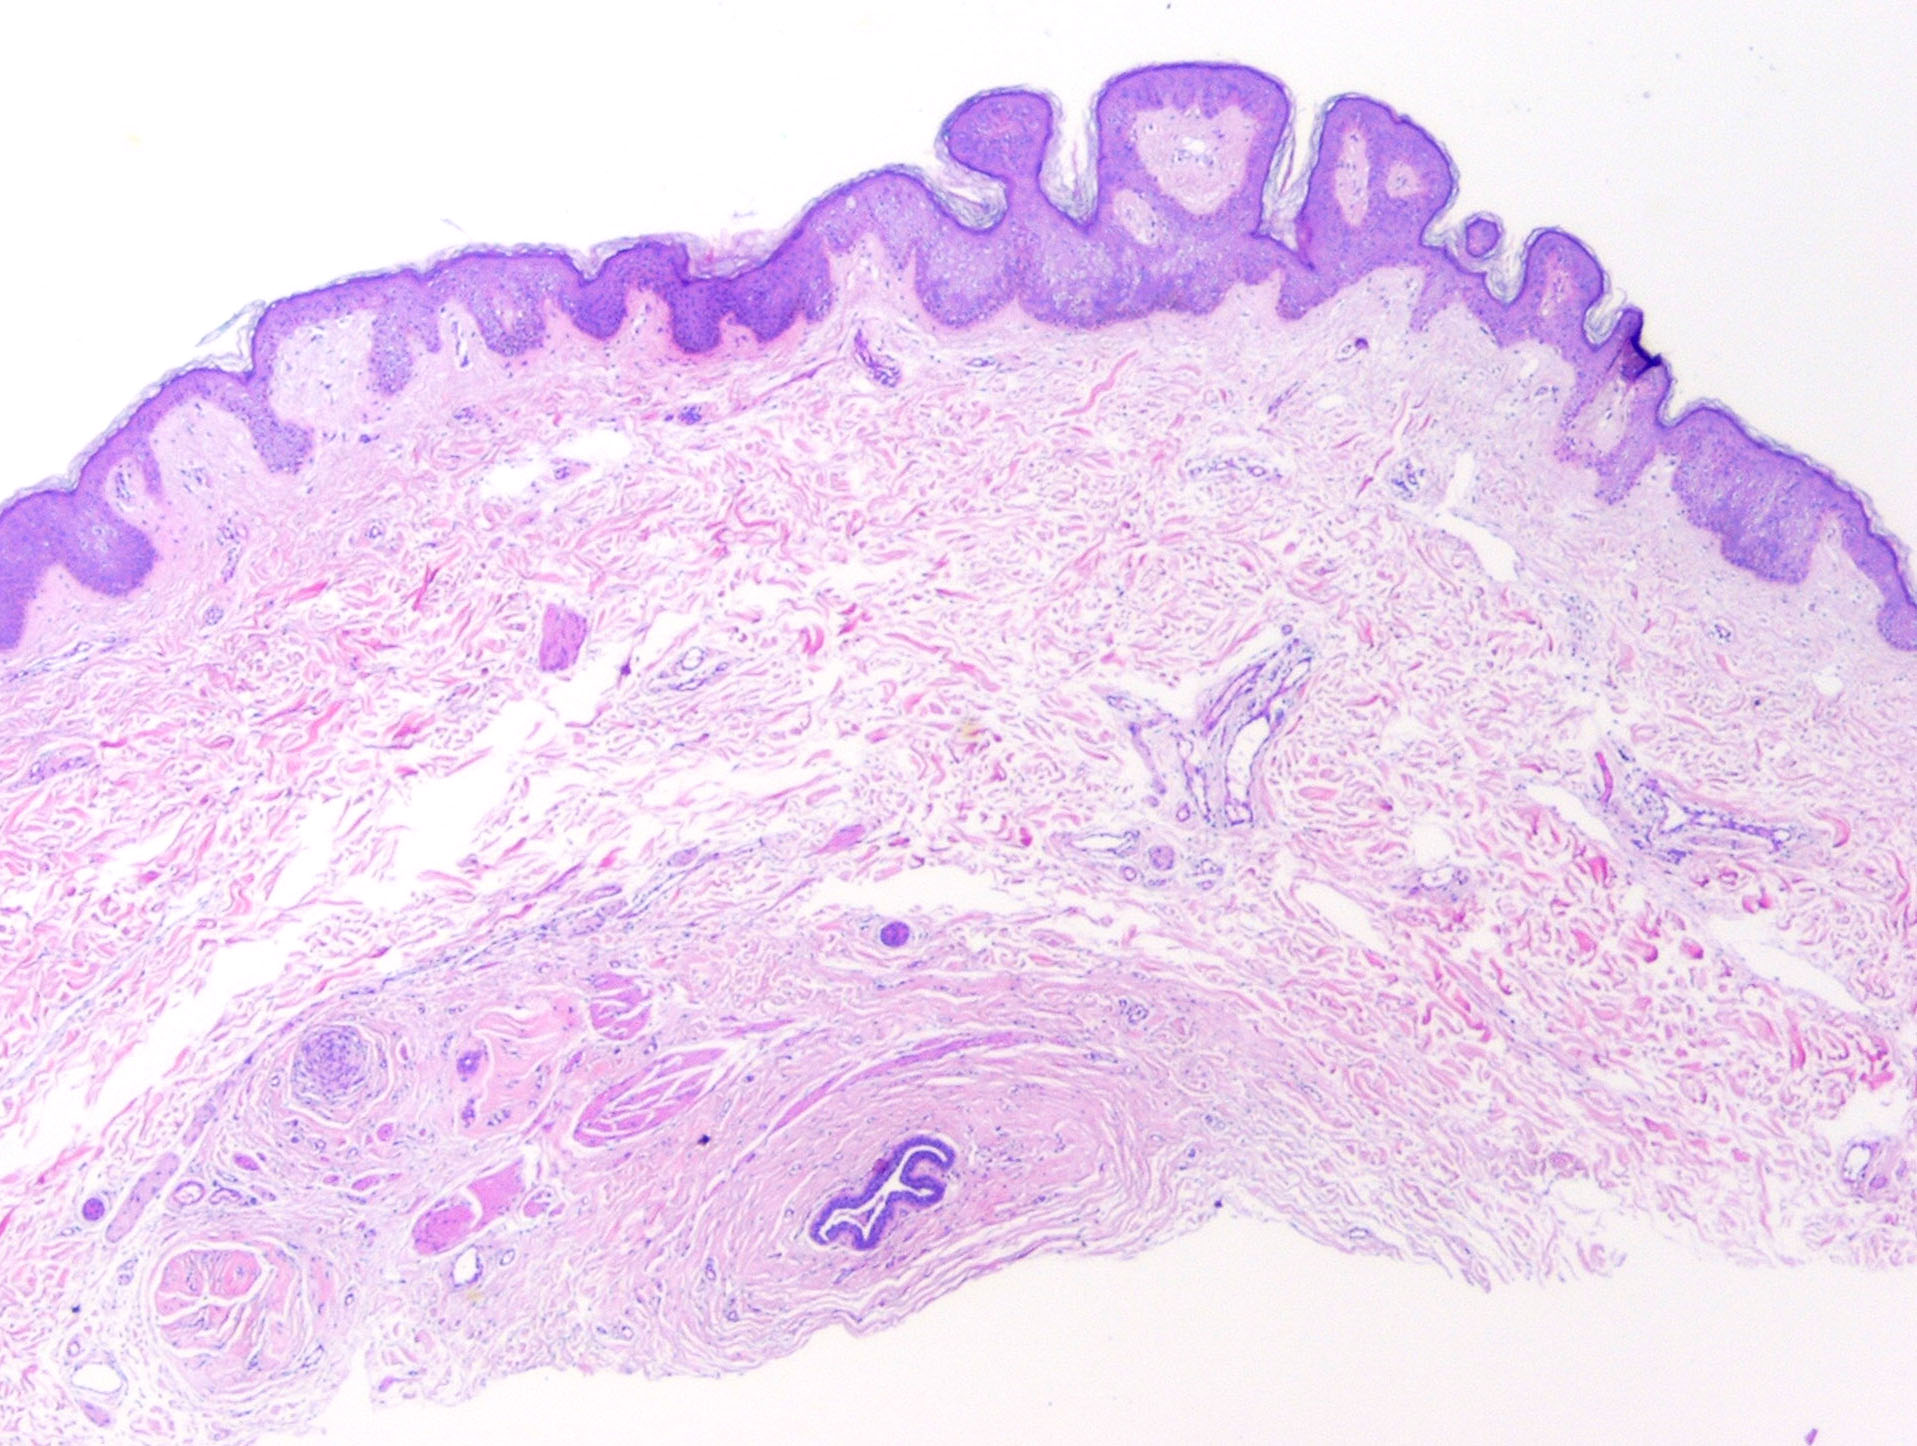

Accessory Nipple

The histologic features of a supernumerary nipple are identical to that of the regular nipple, including hyperpigmentation, slight hyperkeratosis with epidermal thickening, pilosebaceous structure of Montgomery areolar tubercles, smooth muscle bundles typical of the areola, and possible mammary glands and intradermal straight ducts.37 A significant increase in the number of clear cells of Toker has been found in supernumerary nipple tissue, indicating supernumerary nipple may be a precursor of extramammary Paget disease